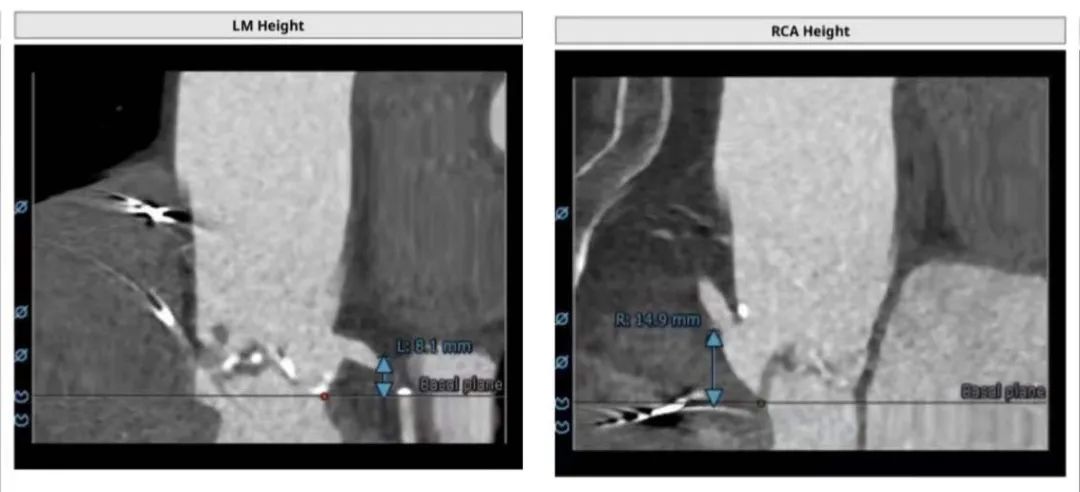

患者为三叶瓣,中重度钙化,右冠高度可,但左冠高度8mm,且瓣叶达到冠脉开口上缘,法式窦结构不大,综合考虑冠脉风险高。

湖州市中心医院程震锋主任TAVR团队和浙大二院刘先宝主任团队,共同讨论分析,手术拟右侧股动脉作为主入路,使用22mm球囊预扩,根据球囊预扩情况,进一步确认冠脉风险。选偏小一号L26号的VenusA-Valve瓣膜,并采用VenusA-Plus可回收输送系统确保瓣膜的稳定释放,瓣膜释放后结合造影和超声情况,决定是否后扩。 考虑该病例存在高风险,决定必要时采取冠脉保护措施。